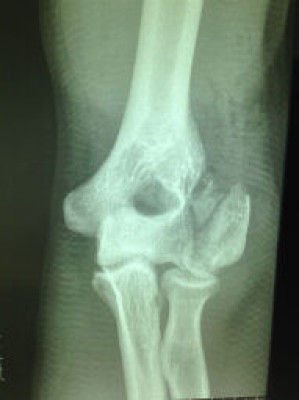

Fractura de Codo - Antes